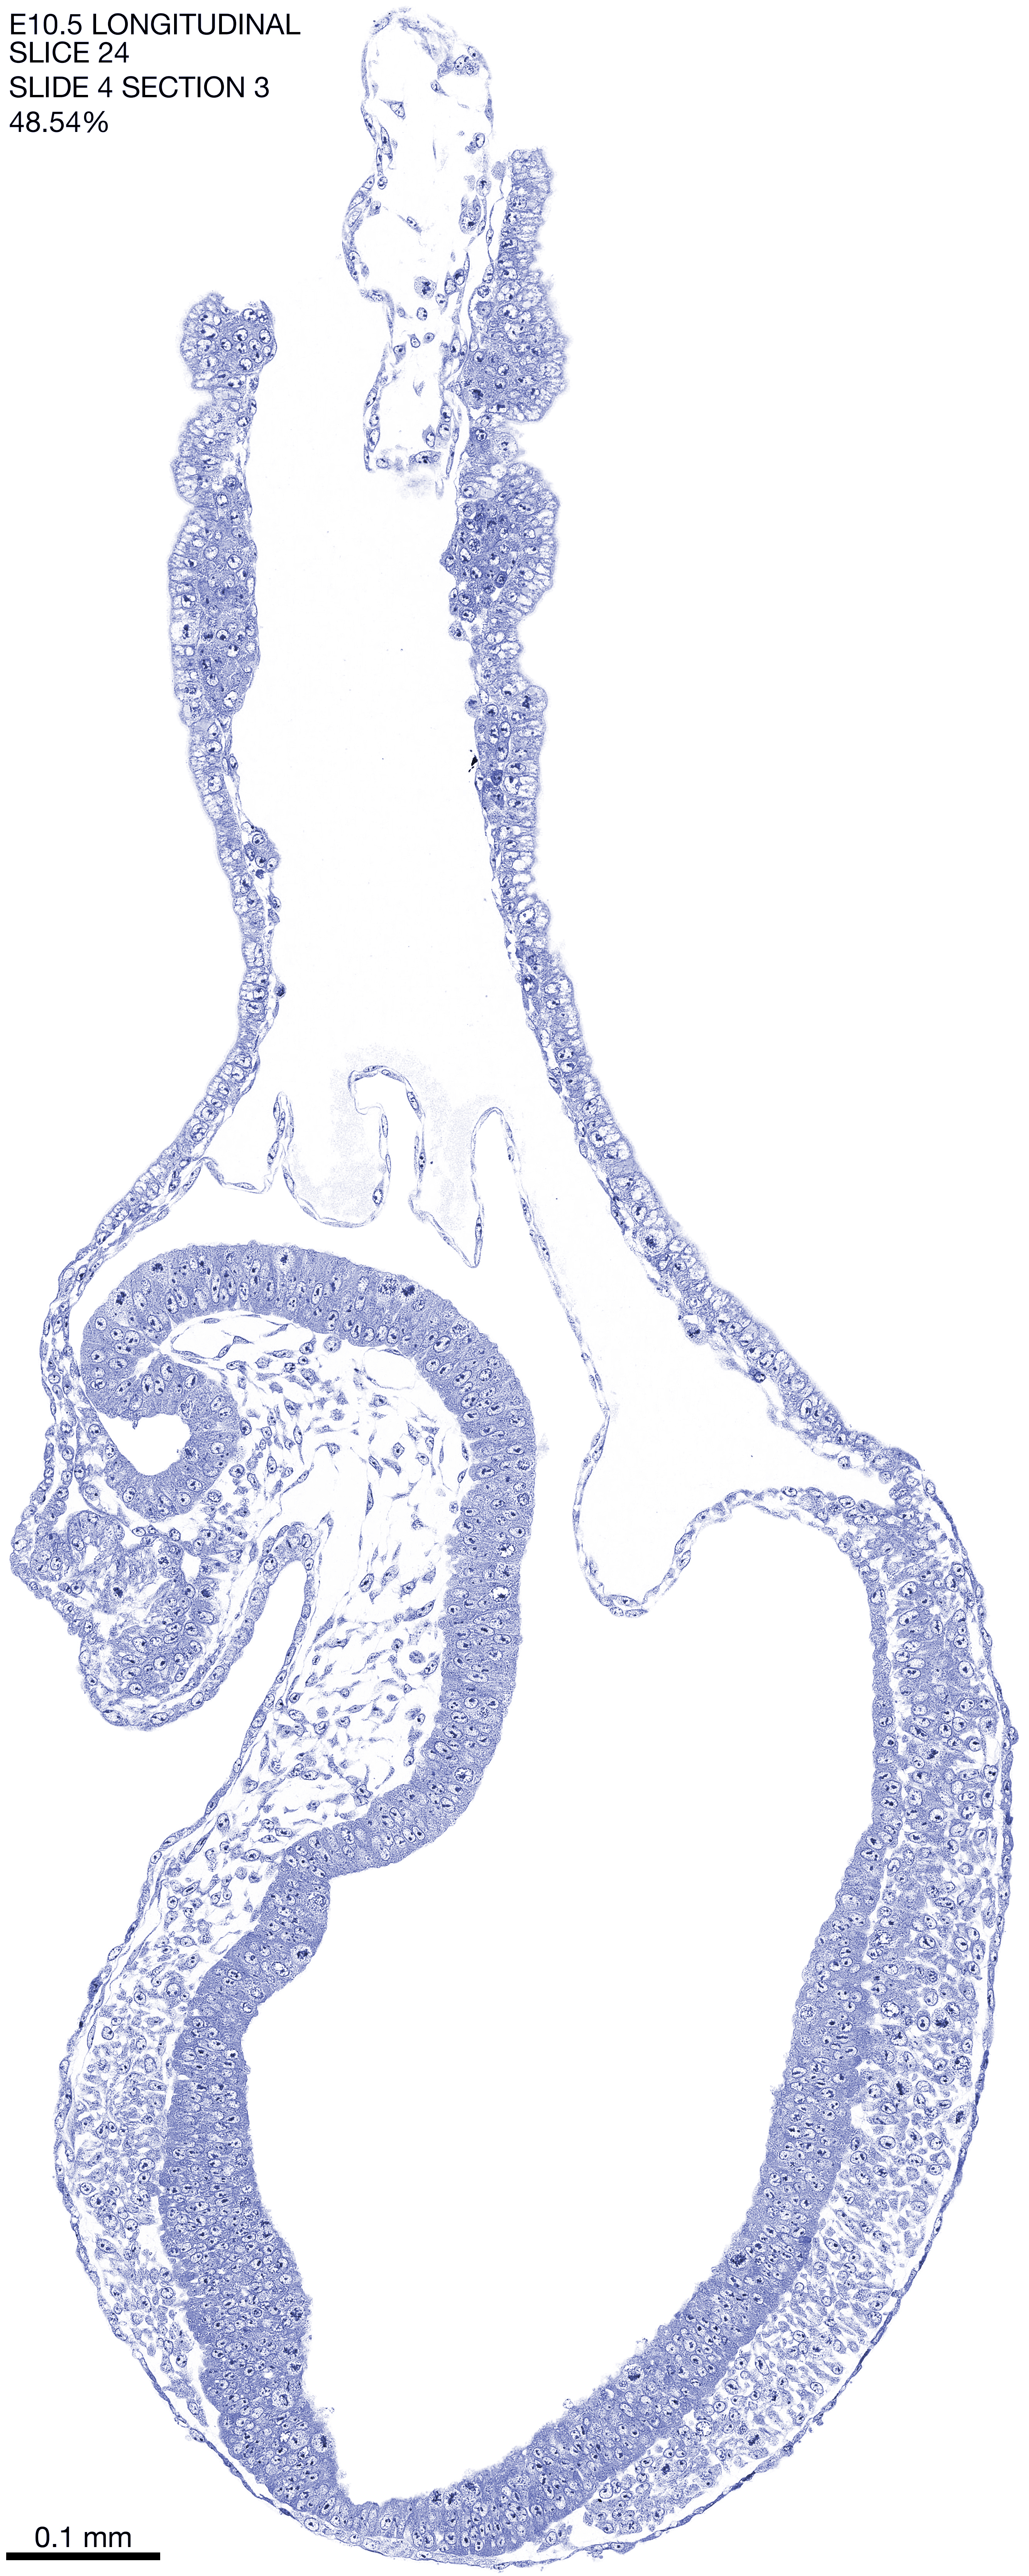

E10.5 Longitudianal Archive This page contains jpg files of ALL SLICES (each 3µm thick) that were scanned of the E10.5 longitudinally cut specimen. Download: Large | High Res Download: Large | High Res Download: Large | High Res Download: Large | High Res Download: Large | High Res Download: Large | High Res Download: Large | High Res Download: Large | High Res Download: Large | High Res Download: Large | High Res Download: Large | High Res Download: Large | High Res Download: Large | High Res Download: Large | High Res Download: Large | High Res Download: Large | High Res Download: Large | High Res Download: Large | High Res Download: Large | High Res Download: Large | High Res Download: Large | High Res Download: Large | High Res Download: Large | High Res Download: Large | High Res Download: Large | High Res Download: Large | High Res Download: Large | High Res Download: Large | High Res Download: Large | High Res Download: Large | High Res Download: Large | High Res Download: Large | High Res Download: Large | High Res Download: Large | High Res Download: Large | High Res Download: Large | High Res Download: Large | High Res Download: Large | High Res Download: Large | High Res Download: Large | High Res Download: Large | High Res Download: Large | High Res Download: Large | High Res Download: Large | High Res Download: Large | High Res Download: Large | High Res Download: Large | High Res Download: Large | High Res Download: Large | High Res Download: Large | High Res Download: Large | High Res Download: Large | High Res Download: Large | High Res Download: Large | High Res Download: Large | High Res Download: Large | High Res Download: Large | High Res Download: Large | High Res